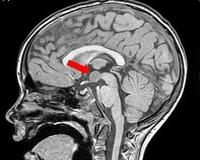

• МРТ головного мозга. На снимках МРТ отображается объемное образование однородной структуры с четкими контурами, в котором не накапливается контрастное вещество, отсутствуют признаки инвазивного роста. При обследовании в режиме Т1 очаг гипоинтенсивный, а в режиме Т2 - переменный гиперинтенсивный.